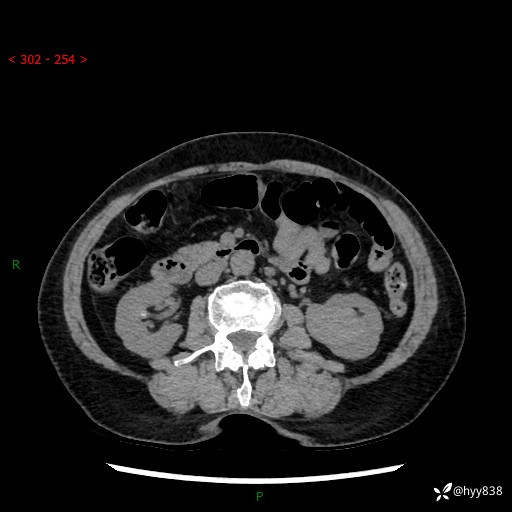

72岁/女,检查发现左肾占位1天。为了满足诊断,常规四期后,又加了延迟期-结果公布~

【患者信息】:72岁/女

【主诉】:检查发现左肾占位1天

【现病史及既往史】:患者于1天前检查发现左肾占位,无畏寒发热,无咳嗽咳痰,无腰腹部疼痛不适,无肉眼血尿、无尿频尿急症状,起病来,患者未行特殊治疗,为求进一步诊治,门诊以"左肾占位"收治入院。 发病来患者精神、饮食、睡眠良好,小便如上,大便正常,体重无明显变化。

【检查】:肾脏CT平扫+增强